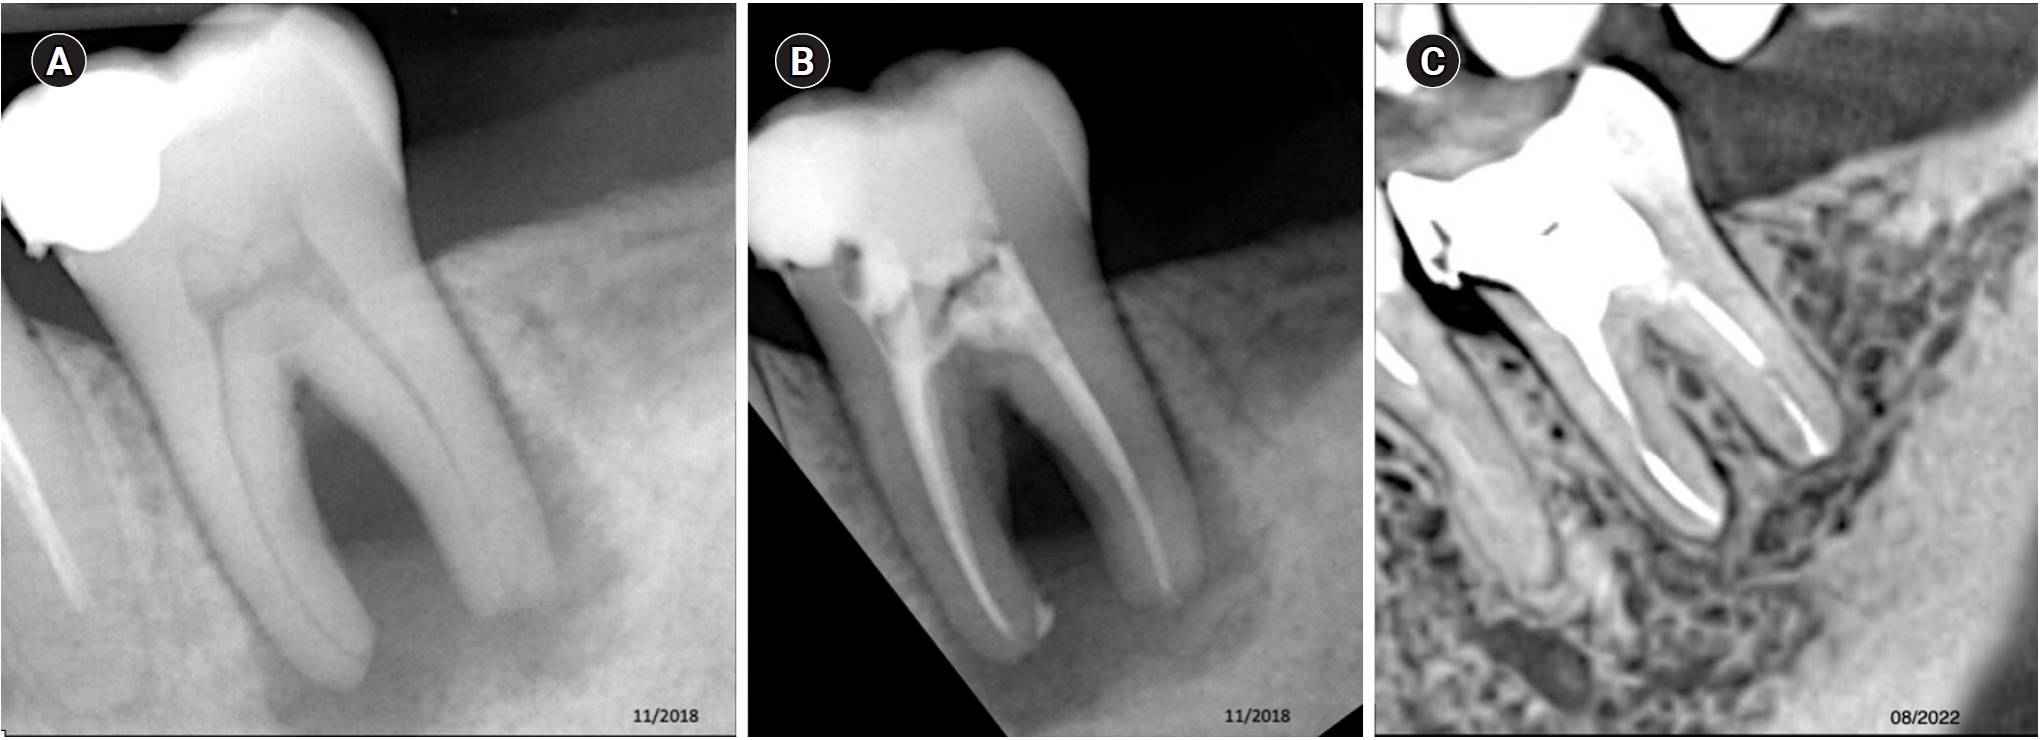

Tooth 36 with a diagnosis of previously treated with symptomatic apical periodontitis. (A) Diagnostic X-ray. (B) Immediate after obturation. (C) Tomographic control after 40 months, showing the apical lesion in the same manner as in the initial X-ray, considered a failure.